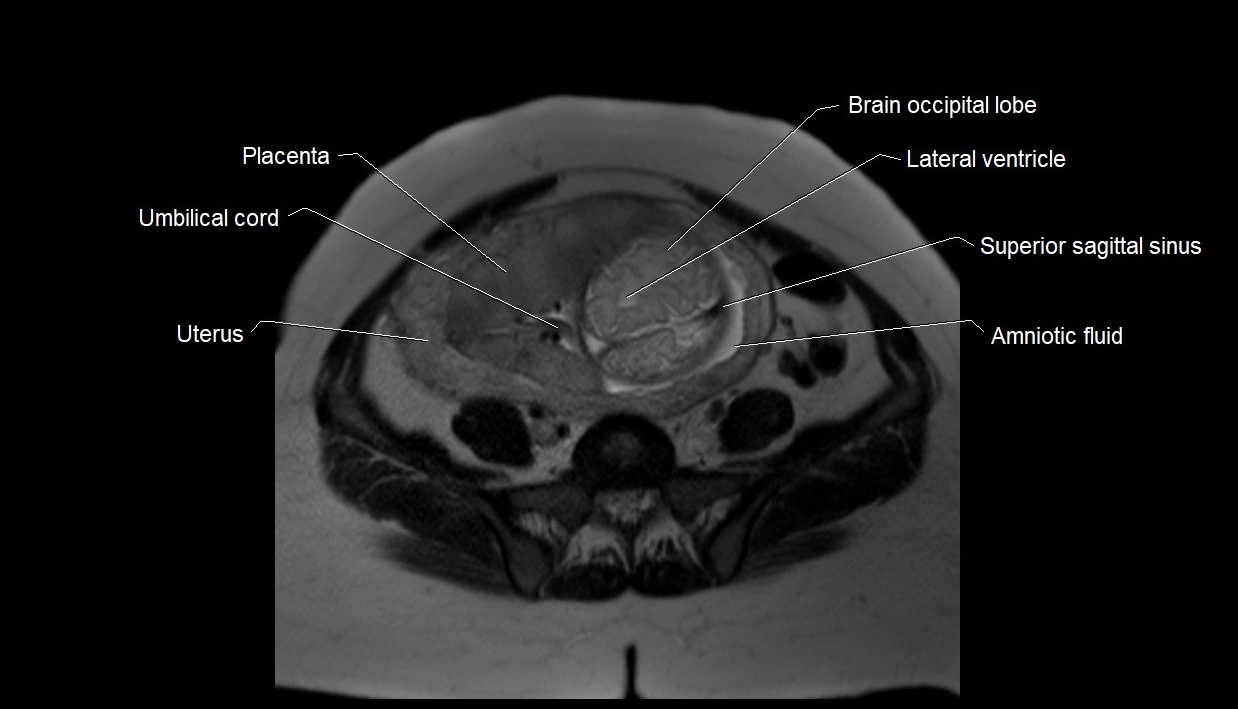

MRI Appearance

T2 HASTE (T2 GRE):

• Amniotic fluid shows very bright hyperintense signal

• Provides natural contrast against fetus and placenta

• Small particles (vernix) may appear as scattered hypointense foci within bright fluid

MRI image

image